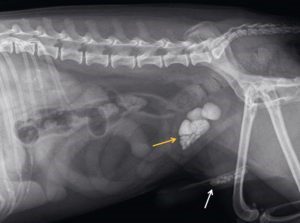

Of en waar de steentjes precies zitten kan met behulp van echografie of röntgenfoto’s in beeld worden gebracht. Helaas zijn niet alle typen stenen op een röntgenfoto goed zichtbaar (zie figuur 2), daarom wordt in veel gevallen gekozen voor echografisch onderzoek.

Figuur 2: Röntgenfoto van een reu met zowel steentjes in de blaas als in de plasbuis. In dit geval betreft het calciumoxalaat stenen welke goed Okidoki, die regelmatig met echografie wordt gecontroleerd in verband met blaassteentjes. zichtbaar zijn op de röntgenfoto.